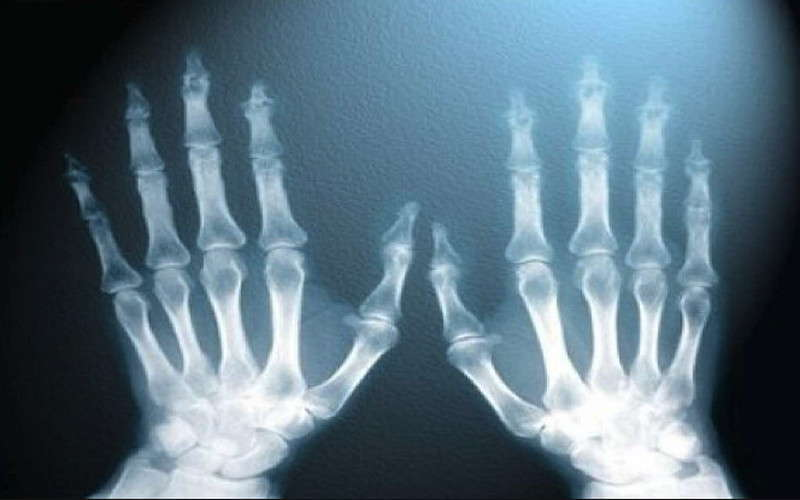

Он уже и забыл, что собирался домой. Оставив чехол на трубке, Рентген стал ходить с экраном в руках по лаборатории и наблюдать, что происходит. Оказывается, что в полутора-двух метрах от трубки непонятное излучение от нее легко достигает экрана и заставляет его светиться. Причем ни бумага, ни дерево, ни стекло этому излучению не преграда. Когда случайно он поместил на пути невидимого луча свою руку, на экране он увидел контуры своих костей.

Оказалось, что с помощью рентгеновских лучей возможно не только исследовать внутренний мир человека, но и заглянуть внутрь кристаллов.

Перечислить все области, где применяются рентгеновские лучи сложно, они используются от медицины до астрономии.